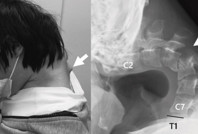

Sürekli telefonuna bakan 25 yaşındaki gencin boynu yamuldu Sürekli telefonuna bakan 25 yaşındaki bir adam, yaşadığı sağlık sorunuyla tıp literatürüne girdi.